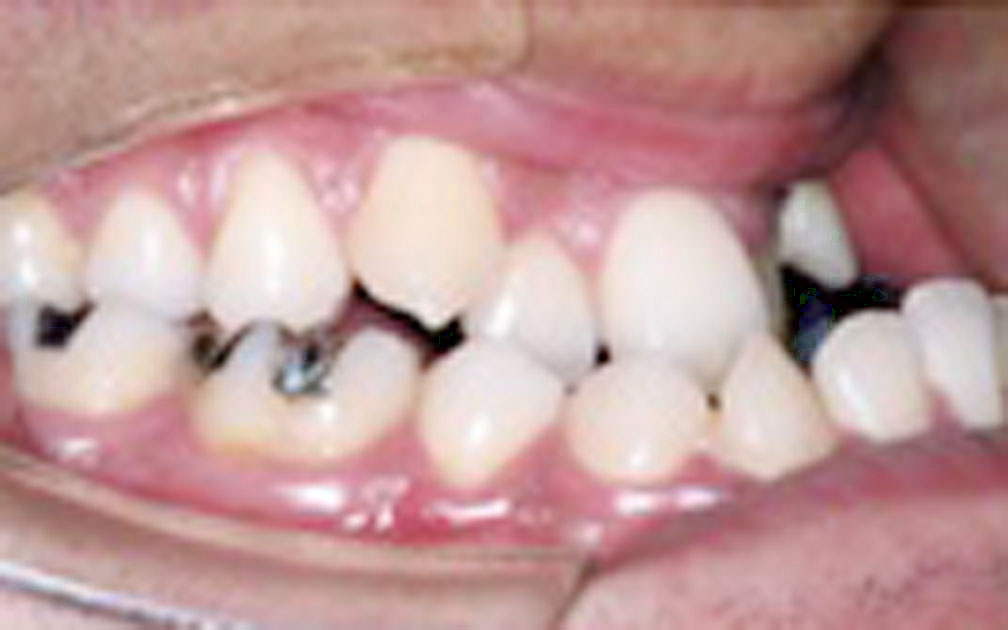

矯正の症例3 (診断名)叢生(ソウセイ)

(患者様の主訴)八重歯が気になる

(治療開始年齢)23歳4カ月

(主な治療装置)エッジワイズアプライアンス

(抜歯部位)上下第1小臼歯4本抜歯

(治療期間)1年10カ月

(治療費)¥805000

(個別リスク・副作用)叢生が著しいため動的治療後長期にわたる保定が必要となる。

歯牙の移動量が大きいため歯根が短根になるリスクがある。

叢生が改善されるまで、ブラッシングがしにくい状態が続くために齲蝕になるリスクがある